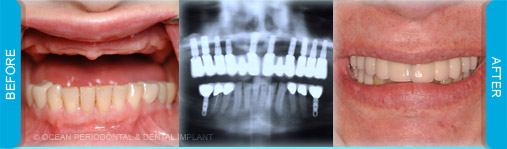

Dental implants are commonly used to replace missing or lost teeth in order to ensure patient comfort, function, and aesthetics. Indeed, there are many treatment options for management of missing teeth, such as bridges, and partial/complete dentures.

Nonetheless, numerous studies have demonstrated that implant-supported restorations are generally deemed to have superior functional and aesthetic outcomes. Furthermore, there are cases where dental implants may be the only logical choice for the restoration of function and aesthetics.